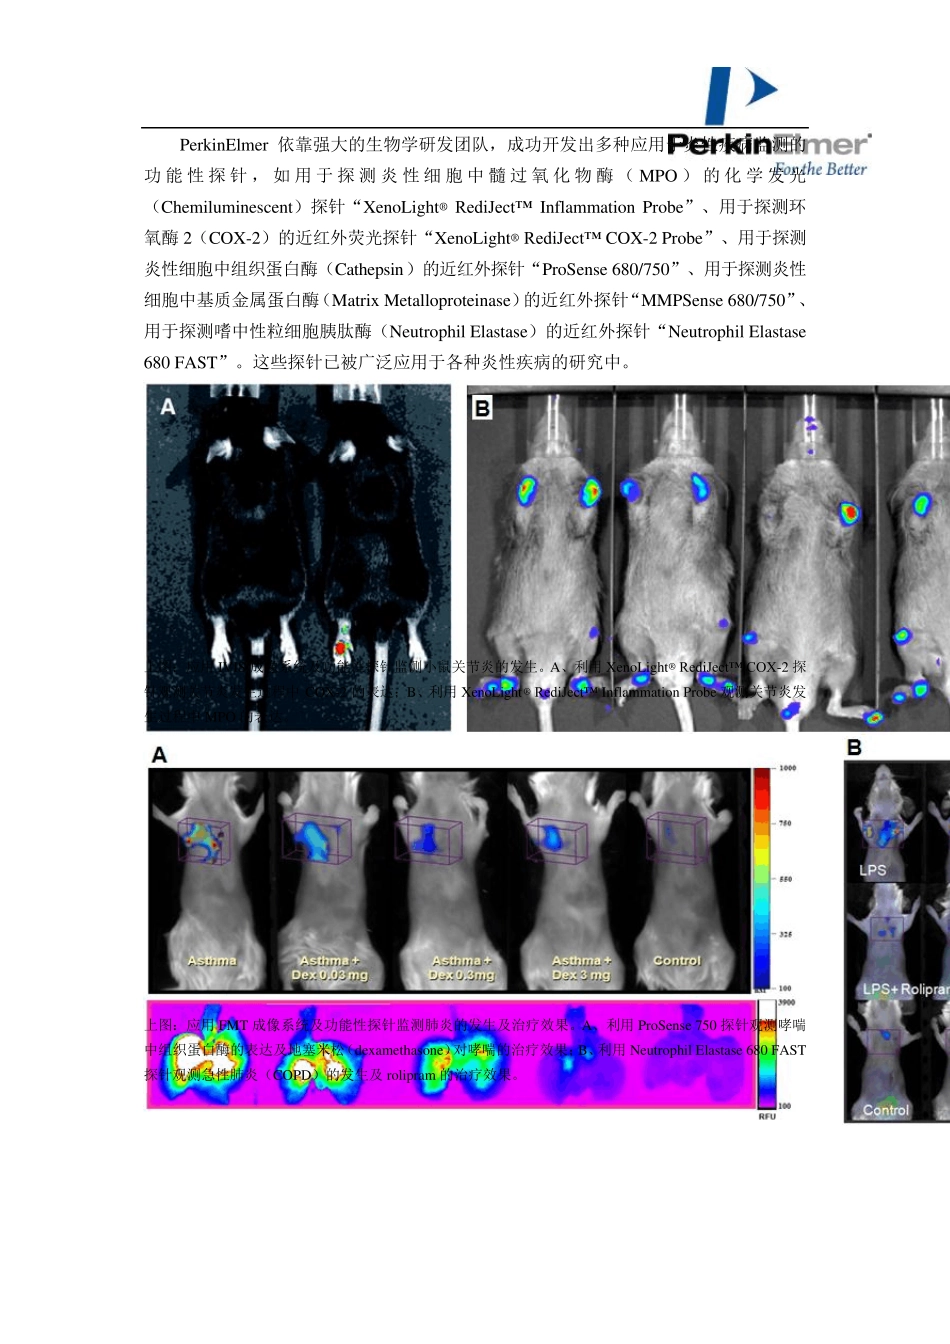

小动物活体光学成像技术在免疫学研究中的应用 PerkinElmer 小动物活体光学成像技术已在生命科学基础研究、临床前医学研究及药物研发等领域得到广泛应用。在众多应用领域中,免疫研究是活体光学成像技术的应用热点之一。在应用活体光学成像技术进行免疫学研究中,常用的标记方法及应用领域包括:1、利用功能性探针监测免疫疾病的发生发展及相关治疗;2、利用荧光素酶基因或荧光染料标记免疫细胞,监测免疫细胞的免疫应答作用;3、利用荧光素酶作为报告基因标记疾病相关基因构建转基因动物,进行免疫疾病机理研究。下面结合一些具体实例进行阐述: 一. 监测免疫疾病的发生发展及治疗效果 伴随免疫疾病研究的深入,目前已开发出一系列针对免疫疾病监测的功能性探针,这些探针的设计大多是基于在免疫疾病中表达的特征性分子或酶,通过对特征性分子或酶的监测而反映疾病的发生发展。利用这些探针并结合活体光学成像技术,研究者可以方便快捷地在活体动物水平监测免疫疾病的发生发展及治疗效果。 如在各种炎性疾病的发生发展中,通常会伴随大量活性氧自由基(ROS)及氧化胁迫的产生。研究者根据上 述特征,设计出能够 特异 性探测 ROS 或氧化胁迫相关酶的功能性探针用于炎性疾病的检 测。Lee 等应用其 自行研发的表面结合透 明 质 酸 的金 纳 米 颗粒 (HA-AuNPs)成功检 测了 小鼠 关节 炎的发生。该 纳 米 颗 粒 表面结合了 荧光染料标记的透 明 质 酸 ,当 未 被 激 活时 ,由于荧光染料及纳 米 颗 粒 本 身 的相互 作用而处 于荧光湮 灭状 态 ,而表面结合的透 明 质 酸 一旦 被ROS 或透 明 质 酸 酶剪 切 ,便会被 外 界 光源 激 发而发光。应用该 探针并结合活体光学成像技术,便可在活体动物水平灵 敏 监测到炎性疾病的发生。 上 图 :应用HA-AuNPs 及 IVIS 系统 观 测小鼠 四 肢 关节 炎的发生。尾 静 脉 注 射 探针,不 同 时 间 点观 测。 PerkinElmer 依靠强大的生物学研发团队,成功开发出多种应用于炎性疾病监测的功能性探针,如用于探测炎性细胞中髓过氧化物酶(MPO )的化学发光(Chemiluminescent)探针“XenoLight® RediJect™ Inflammation Probe”、用于探测环氧酶2(COX-2)的近红外荧光探针“XenoLight® RediJect™ COX-2 Probe”、用于探测炎性细胞中组织蛋白酶(Cathepsin)的近红外探针“ProSense 680/750”、用于...